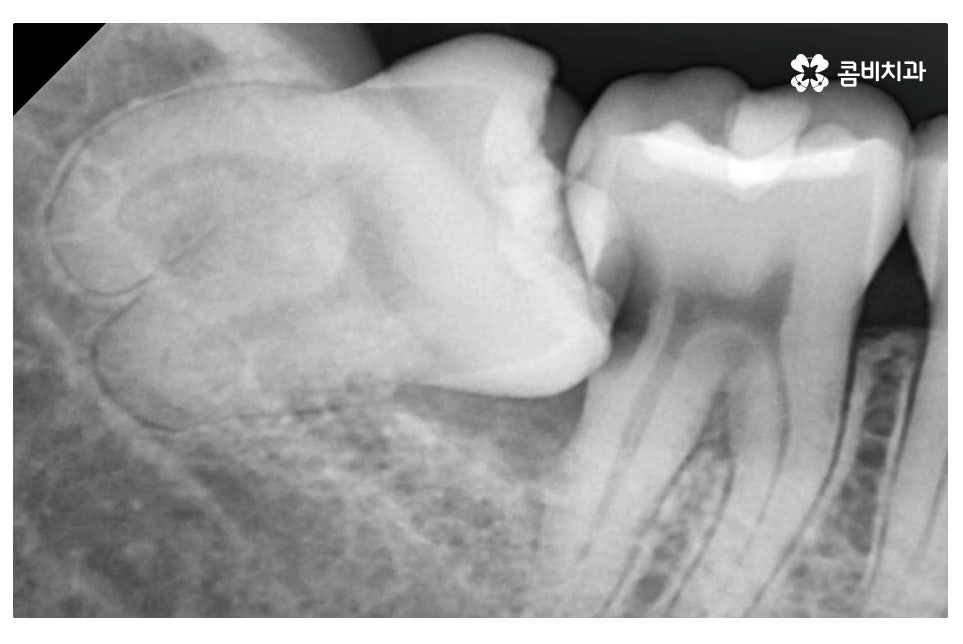

오늘 보여드린 환자분의 케이스는 사랑니로 인해 어금니에도

충치가 발생한 사례로 이처럼 치아 사이에 충치가 발생하면

치아의 하단부, 안쪽에 손상이 발생하기 때문에

어금니 신경치료를 하게 되는 경우로 이어질 수 있어요.

위처럼 누운 사랑니의 경우 단지 사랑니의 발치 만으로 끝나는 것이 아니라

주변 치아, 평생 지켜야 할 어금니 손상을 유발할 수 있기 때문에

엑스레이 사진에서 보시는 것처럼 사랑니로 인해 어금니 옆 부분에

충치가 발생되었고 사랑니 발치 후 어금니 신경치료를 하여

자연치아의 손상이 커진 케이스라고 할 수 있는데요